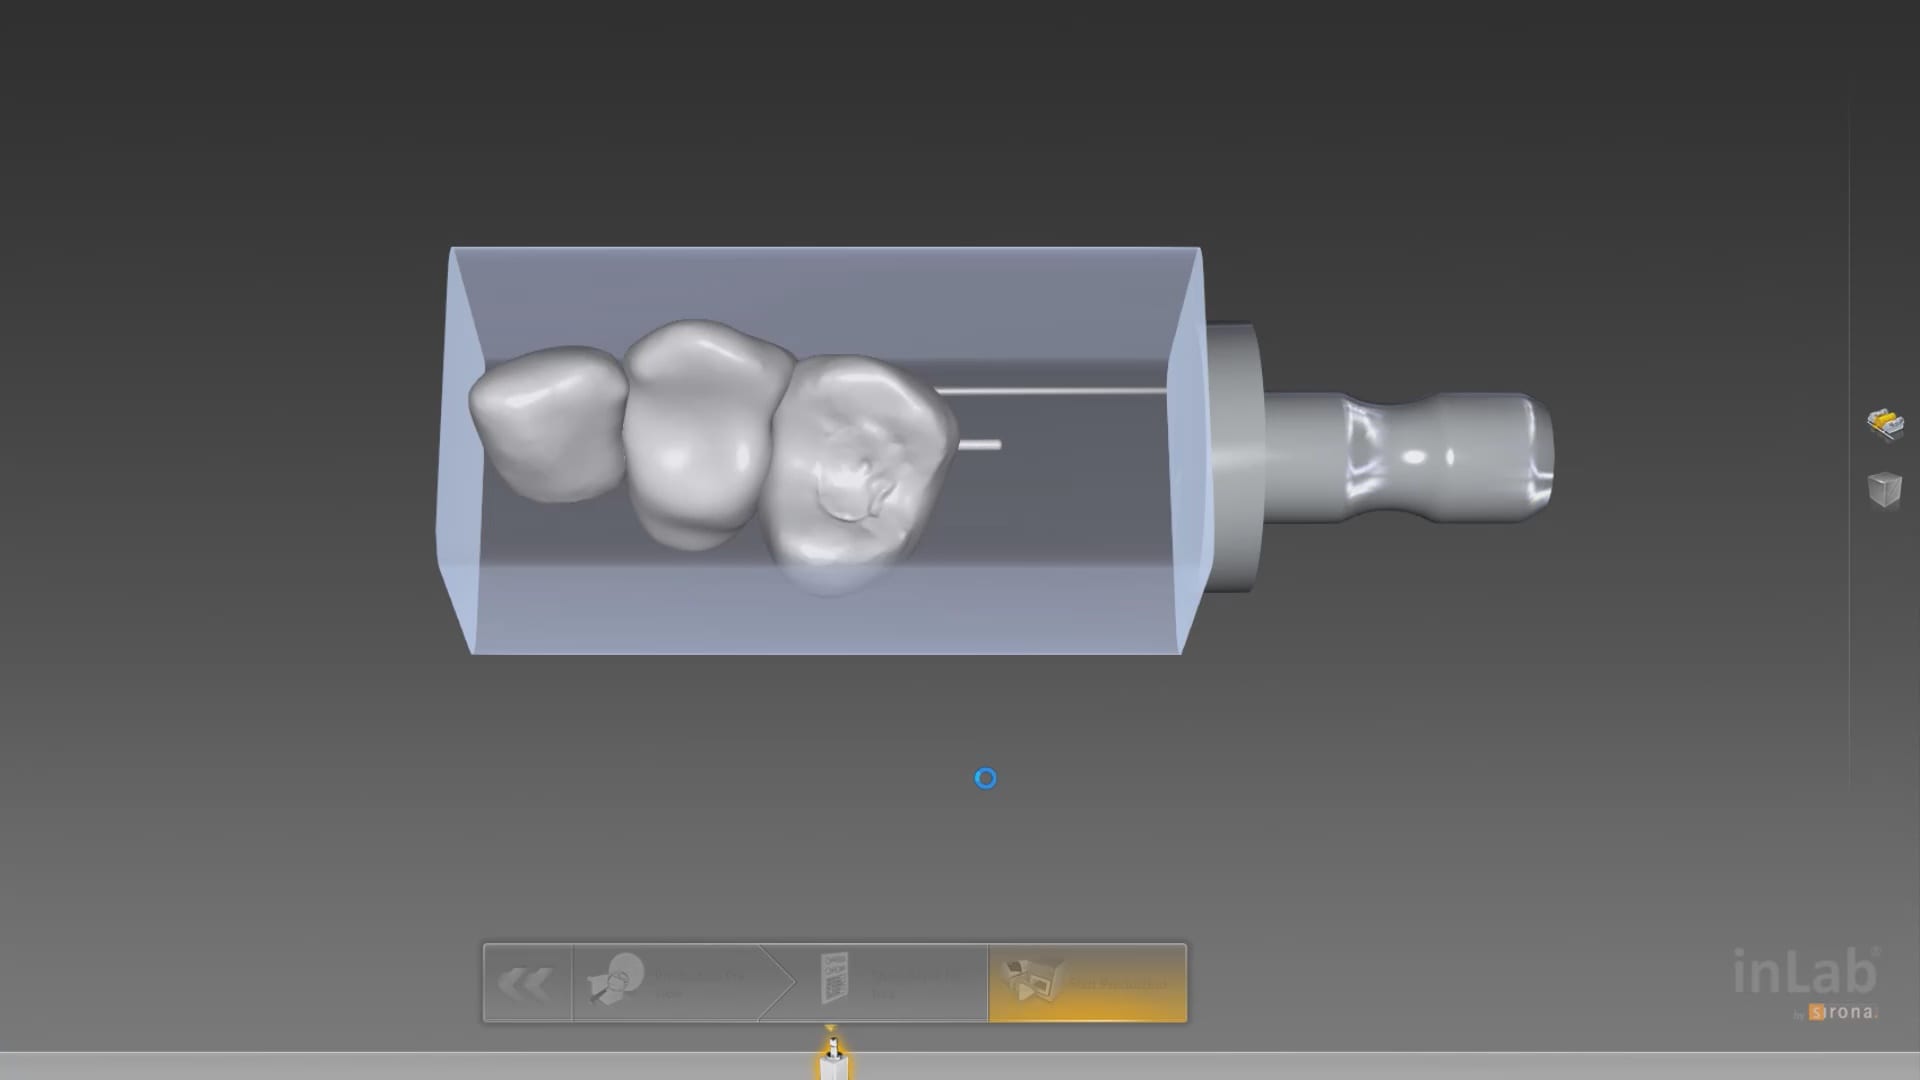

Full Arch Scan by The Shining 3D Aoralscan

March 16, 2020In this video we demonstrate how the Aoralscan can complete a full arch scan utilizing the basic principles of digital impressioning. Proper retraction, isolation, and scanning technique lead to high […]